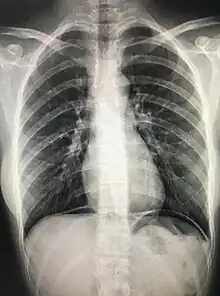

The cupola sign is seen on a supine chest or abdominal radiograph in the presence of pneumoperitoneum.

It refers to dependent air that rises within the abdominal cavity of the supine patient to accumulate underneath the central tendon of the diaphragm in the midline. It is seen as lucency overlying the lower thoracic vertebral bodies. The superior border is well defined, but the inferior margin is not.